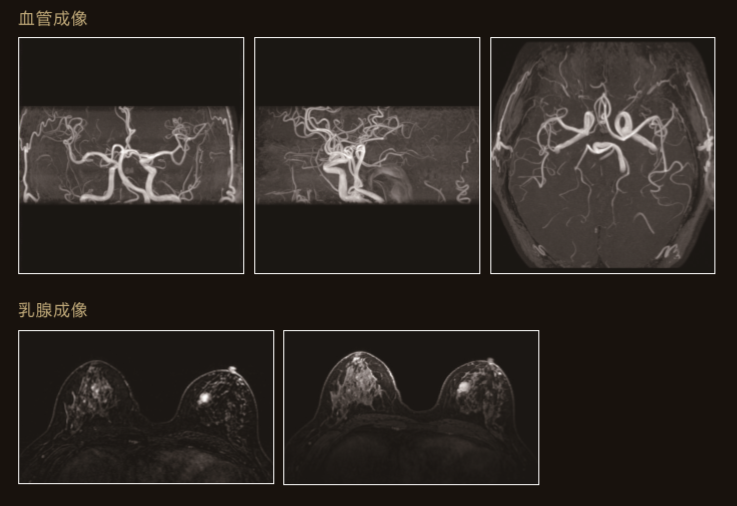

臨 床 圖 集

可配備更充實的新檢查功能更好的觀察狹窄血管的血液動态變化

利用搏動引起的血液流速變化進行下肢無造影劑拍攝MRA技術

利用水和脂肪的周波數差異和磁化率變化進行的脂肪抑制

T2值得變化可以通過彩色圖表示從而達到更好的組織變性的目測性